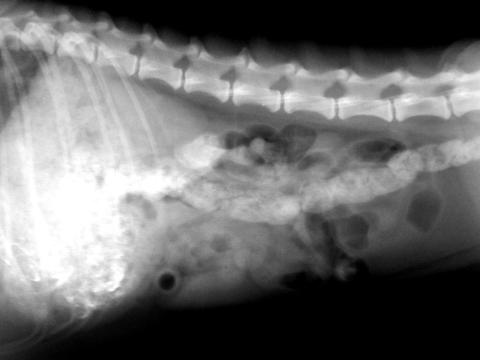

本来は、内蔵カメラで撮影した場合、白のところが青みがかっているのですが、それは最初にモノクロにしてあります。

これだけだと、生のレントゲン写真を単に小さくして持ち歩きやすくするだけになります。

しかし、デフォルトで入っているビューアーでも簡易的な画像処理がかけられるので、使ってみました。

明るさ補正で若干暗くしたものになります。これでも余分な軟部組織がとんで、骨や内蔵がはっきり見られるようになります。

またコントラストを調整すると

黒いところはより黒く、白いところはより白くと画像に強弱が付くようになります。明るさ補正で処理をしたものよりも、さらに骨や内蔵の形態がはっきりと描画されるようになります。

明るさや、コントラストを調整することにより、今まで生のレントゲンでははっきりしなかった、臓器がかぶっている画像を強調して描出できるようになります。

また拡大した画像です

内蔵カメラで撮影したものです。

はっきり見えないかもしれませんが、拡大したときに横にまっすぐな線が入ります。

これは決して異常ではありません。

レントゲンを撮る際には、グリッド(ブレンデともいいます)といわれるX線の散乱線(臓器や骨に当たってレントゲンビームが飛び散る)を抑えるためのものを取り付けて撮影しています。

通常、肉眼ではわかるのですが、通常のデジカメなどで撮影した場合、グリッド線がつぶれてしまうことが多くあります。

それが、拡大したときに多少のつぶれはありますが、明瞭に写っています。

カメラの解像度がかなりいい証拠になります。